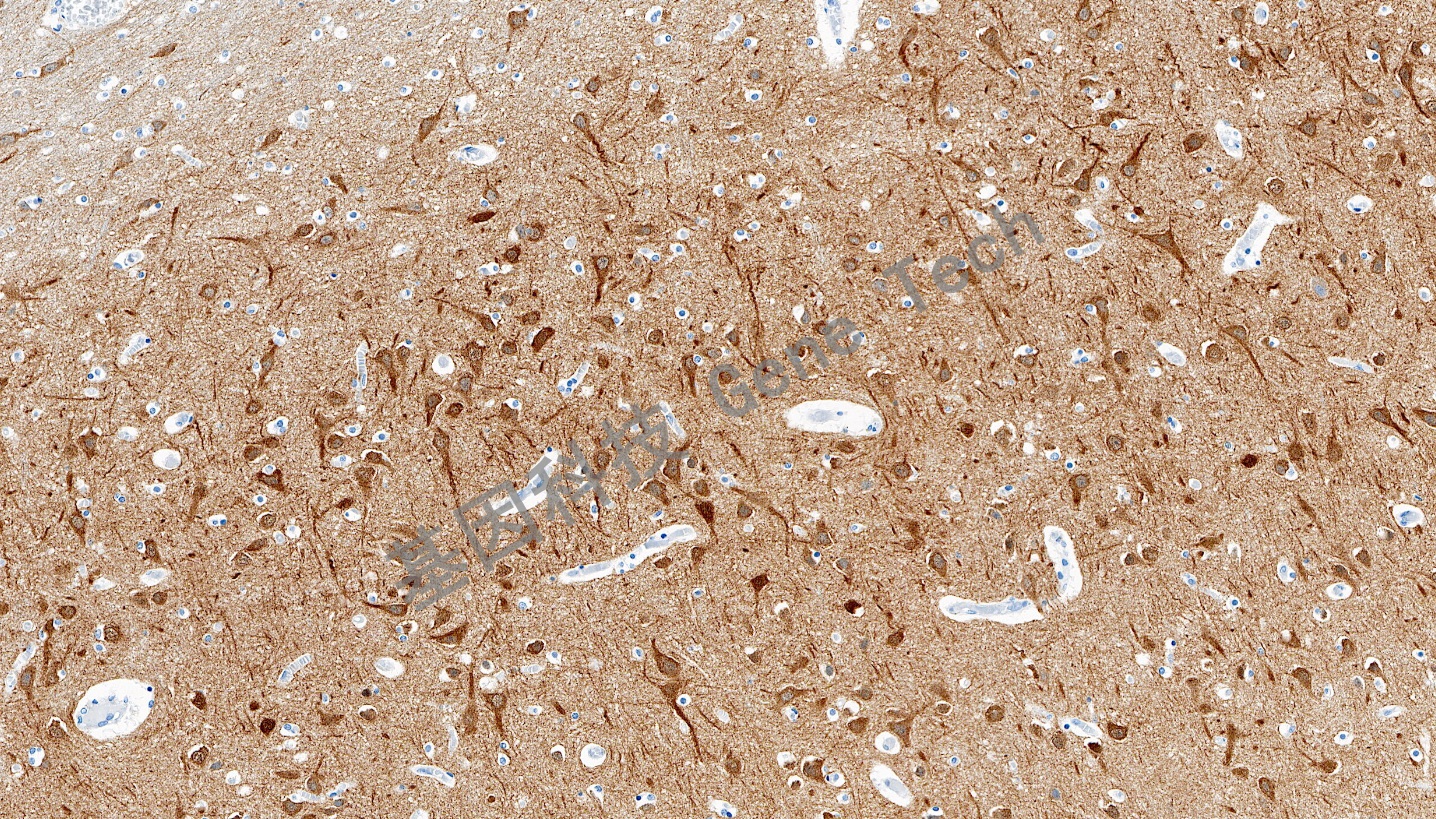

| 预处理:高pH热修复 | 阳性部位:细胞膜/细胞浆 | 阳性对照:脑 |

| 脑石蜡切片,用 DCLK1(GT2565)染色,细胞膜/细胞浆阳性,DAB 显色。 | ||